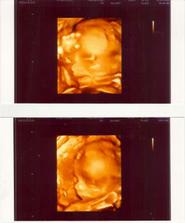

03.10.08 krevní test s HCG 224,6, další kontrola 13.10.08 HCG kolem 8500 a na UTZ 1 krásný gestační váče s krásným žloužkovým viz. foto 🙂))))), 20.0.08 HCG 33200 a tluče srdíčko. Oba s manžílkem máme velikánskou radost!!!